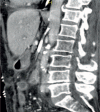

Results: AMI is a vascular emergency that can be successfully treated only within the first hours after the onset of symptoms. Computed tomography angiography is the diagnostic method of choice. Intensive care unit treatment can prevent the occurrence of multiple organ failure. Treatment primarily consists of the revascularization of the mesenteric arteries. Endovascular techniques should be given priority, whereas signs of peritonitis or a central arterial occlusion with high thrombus load primarily require a surgical approach in order to save time and increase patient safety. Additional bowel resections can play a significant role in the treatment of intestinal sepsis.